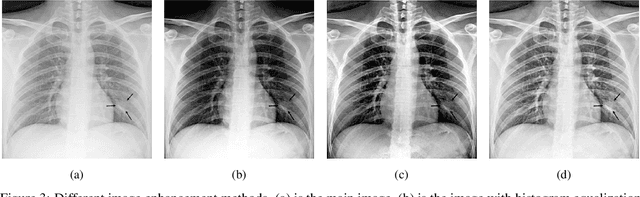

One of the primary clinical observations for screening the infectious by the novel coronavirus is capturing a chest x-ray image. In most of the patients, a chest x-ray contains abnormalities, such as consolidation, which are the results of COVID-19 viral pneumonia. In this study, research is conducted on efficiently detecting imaging features of this type of pneumonia using deep convolutional neural networks in a large dataset. It is demonstrated that simple models, alongside the majority of pretrained networks in the literature, focus on irrelevant features for decision-making. In this paper, numerous chest x-ray images from various sources are collected, and the largest publicly accessible dataset is prepared. Finally, using the transfer learning paradigm, the well-known CheXNet model is utilized for developing COVID-CXNet. This powerful model is capable of detecting the novel coronavirus pneumonia based on relevant and meaningful features with precise localization. COVID-CXNet is a step towards a fully automated and robust COVID-19 detection system.